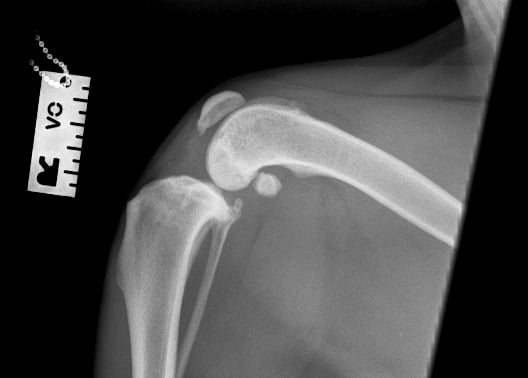

Orthogonal radiographs revealed findings consistent with cranial cruciate ligament disease. The lateral view of the affected limb (Fig. 2) shows joint effusion along with degenerative changes suggestive of osteoarthritis affecting the distal pole of the patella, proximal trochlear groove, and fabellae. The contralateral (left) stifle (Fig. 1) appears normal and serves as a reference. A cranial drawer test was performed under sedation and yielded a positive result.

Fig. 1

Fig. 2